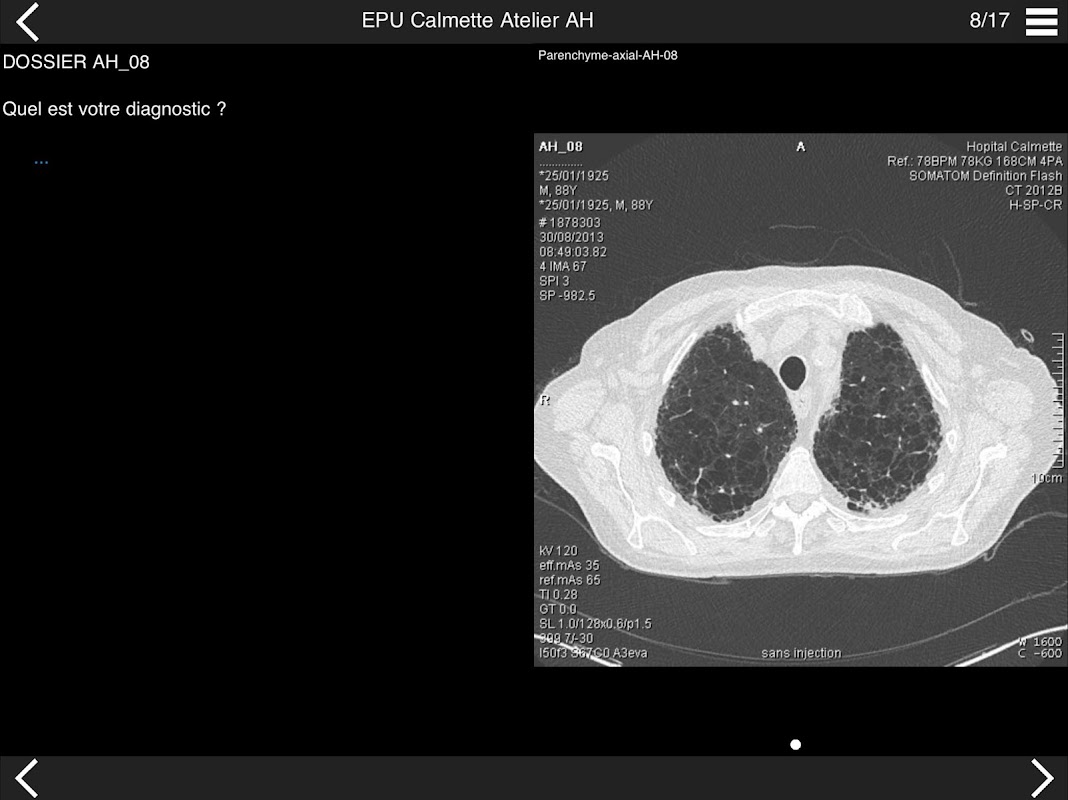

Retrouvez les cas cliniques du Cours intensif de TDM multicoupe du thorax dans cette application.

• DE LA SéMIOLOGIE AU COMPTE-RENDU

* BPCO et nodules pulmonaires : recommandations en 2017

* Pathologie interstitielle : lésions élémentaires et « patterns »

* Pathologie vasculaire et médiastinale